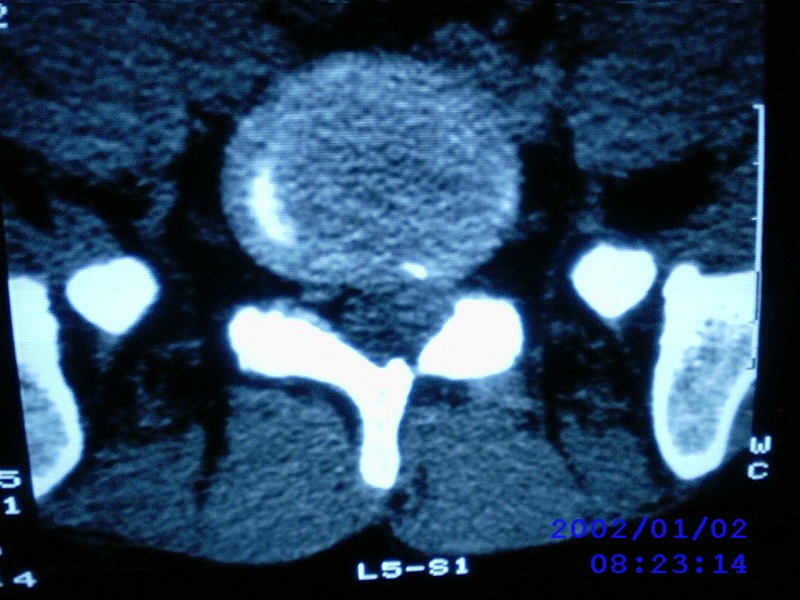

患者,男性,40岁,腰痛伴左下肢疼痛、麻木6年。5年前做过腰椎间盘手术,具体是哪个位置病人记不清了。

我拍的是l4-5、l5-s1

1)l4/5及l5/s1左侧椎板术后改变。2)l5/s1椎间盘突出,l5椎体下缘许莫氏结节。3)l4/5椎间盘膨出并突出。4)l3/4椎间盘膨出。

1)l4/5及l5/s1左侧椎板术后改变。2)l5/s1椎间盘突出,l5椎体下缘许莫氏结节。3)l4/5椎间盘膨出并突出。

1)l4/5及l5/s1左侧椎板术后改变。2)l5/s1椎间盘突出,l5椎体下缘许莫氏结节。3)l4/5椎间盘膨出并突出。4)l3/4椎间盘膨出。支持!